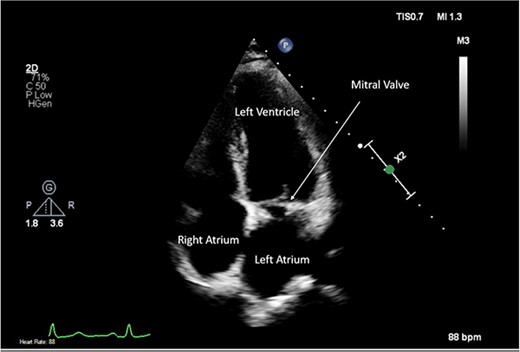

A CTPA was undertaken on Day 2, which excluded pulmonary embolism but confirmed bilateral peri-hilar consolidation and pleural effusions consistent with pneumonia. However, her pulmonary artery was dilated at 32 mm indicative of potential heart failure. On Day 5 of her ICU stay, a transthoracic echocardiogram was undertaken that revealed there to be severe mitral regurgitation including a mobile echogenic mass attached to the underside of the anterior mitral valve leaflet consistent with a vegetation (Figs 1 and 2).

Pre-operative TTE depicting mitral valve with vegetation (labelled).

Intra-operatively, femoral–femoral bypass was established and a 3 cm windsock vegetation was found with a 1.5 × 1.5 cm hole at the aortic inlet on the annular junction. The vegetation travelled from the LV to LA as shown in Figs 3 and 4. The vegetation was excised and the valve debrided, which resulted in moderate regurgitation from severe. Hence, a further 26 mm Physio II ring was placed resulting in no mitral regurgitation. The excised vegetation is shown in Fig. 5 and the post-op TTE images are shown in Figs 6 and 7.